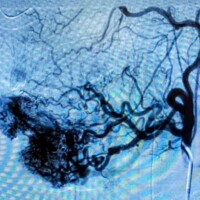

Congenital arteriovenous malformations can be present anywhere in the body but have a predilection for the brain, spinal cord, and the extremities. Rarely arteriovenous malformations of the internal organs such as the kidneys, the intestines, and the lungs can be detected. Early referral to a dedicated center of excellence is key. Diagnosis will inevitably depend on a series of imaging studies such as ultrasound, MRI, and angiography. Treatment is almost always indicated to minimize symptoms and decrease the likelihood of expansion and organ loss. In some rare cases, the malformation has expanded severely enough such that treatment may provide little to no benefit and management is geared more towards palliation of associated symptoms.

The mainstay of treatment for arteriovenous malformation is catheter-based embolization. The term embolization refers to delivery of certain particles or substances as closely as possible into the focus of the arteriovenous malformation. These particles or substances will then act to shut down the malformation by disrupting the blood supply to the focus of the malformation and redirecting blood flow back into the normal circulation. Most commonly, multiple treatment sessions will be required throughout the lifetime of the patient. It is important to emphasize that there is no cure for arteriovenous malformations and that treatment is aimed at minimizing symptoms and slowing the progression of the disease. Even with successful treatment, certain severe cases can continue to expand and cause organ and/or life-threatening problems.

Surgery by and large is not recommended as primary treatment of arteriovenous malformations except in rare refractory cases or to treat associated complications of the malformation.